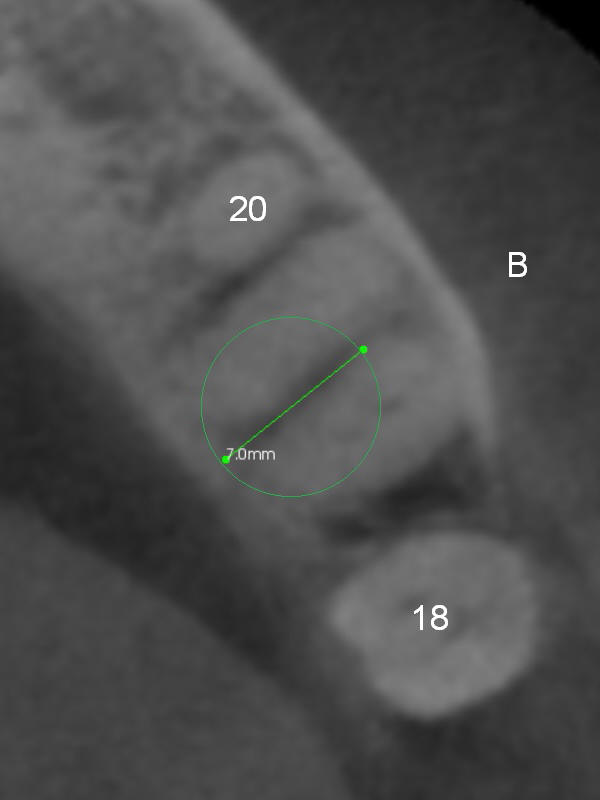

A 71-year-old man (CK) has pain in mastication when the upper left implant treatment is finished. The tooth #19 with distal caries (Fig.1 (CT sagittal section) *) seems to be non-salvageable. The mesial (M) and distal (D) roots appear to be large and closer to the root of the tooth #20 than that of #18. A large implant (7x12 mm) placed in the middle of the socket may increase the chance to invade the root of #20 (Fig.2, 4 (axial section)), as compared to that placed more distal (Fig.3,5).